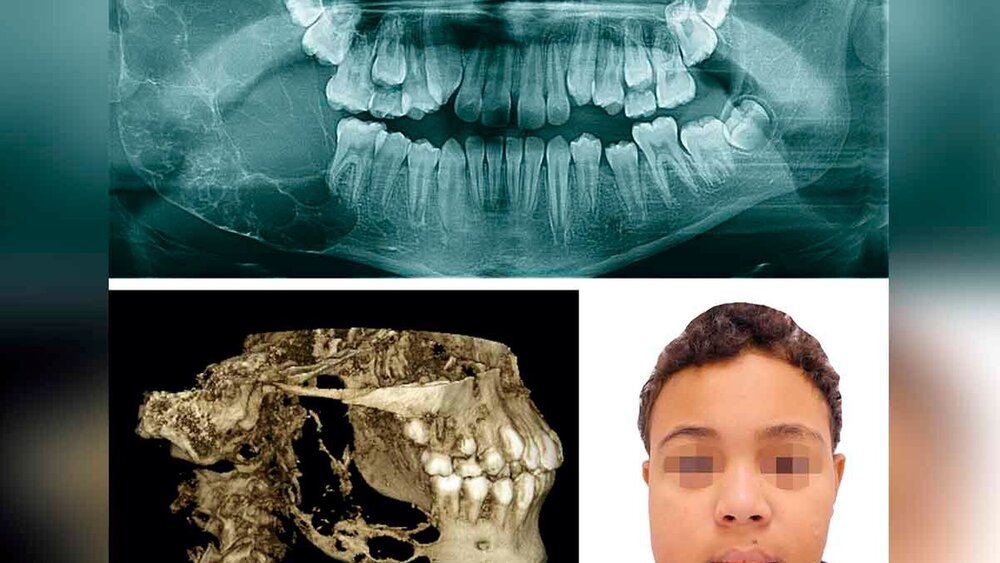

Ein zwölfjähriger Junge wurde uns von seinem Zahnarzt mit einem aktuellen Orthopantomogramm (OPT) zugewiesen. Anamnestisch bestand bei dem ansonsten gesunden Patienten seit ungefähr vier Wochen eine moderate, weiche, nicht schmerzhafte und nicht entzündlich erscheinende Schwellung im Bereich des rechten Unterkiefers. Die Okklusion im Wechselgebiss war ungestört, die maximale Mundöffnung mit 25 mm Schneidekantendistanz (SKD) vermindert. Klinisch war der Zahn 47 im Gegensatz zu den anderen zweiten Molaren nicht erkennbar.

Das OPT und die ergänzend durchgeführte digitale Volumentomografie (DVT) zeigten einen destruierenden, blasig-zystischen Prozess im rechtsseitigen Unterkiefer, der das Kiefergelenkköpfchen praktisch aufgelöst hatte (Abbildung 1). Die Probeexzision von intraoral ergab den Befund eines dentinogenen Geister- oder Schattenzelltumors. Dieser selten vorkommende benigne Tumor zeigt histologisch die namensgebenden „Geisterzellen“ (Abbildung 2).